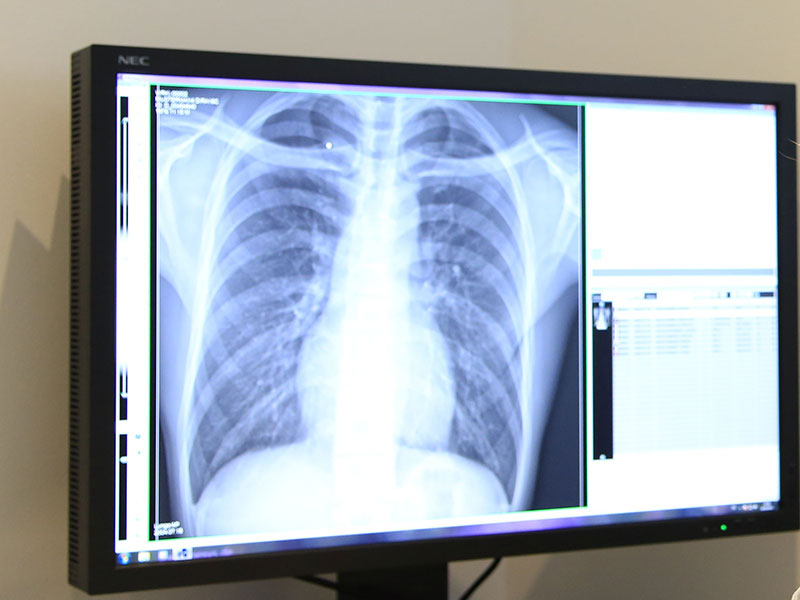

Volldigitale Röntgendiagnostik

Bei bestimmten Erkrankungen oder Verdachtsdiagnosen ist auch heute noch eine Röntgenaufnahme wichtig und notwendig. In unserer Praxis werden keine herkömmlichen Röntgenfilme mehr eingesetzt - wir vertrauen stattdessen der modernen, volldigitalen Röntgentechnik. Diese reduziert die Strahlenbelastung für den Patienten, ermöglicht zusätzliche Informationen und kann in handlicher Form (zum Beispiel auf einem USB-Stick) dem Patienten oder Kliniken zur Verfügung gestellt werden.